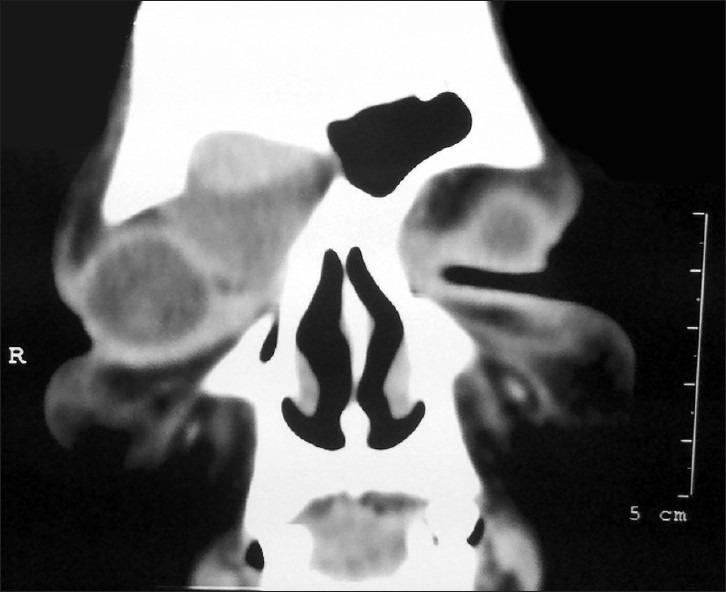

A mucocele of a para-nasal sinus is an accumulation of mucoid secretion and desqua-mated epithelium within the sinus with distension of its walls and is regarded as a cyst like expansile and destructive lesion. If the cyst invades the adjacent orbit and continues to expand within the orbital cavity, the mass may mimic the behavior of many benign growths primary in the orbit. The frontal sinus is most commonly involved, whereas sphenoid, ethmoid, and maxillary mucoceles are rare. Floor of frontal sinus is shared with the superior orbital wall which explains the early displacement of orbit in enlarging frontal mucoceles. Frontal sinus mucoceles are prone to recurrences if not managed adequately. Here, we are evaluating different approaches used to manage various stages of frontal mucoceles which presented to us with orbital complications. Three cases of frontal sinus mucocele are discussed which presented to our OPD with different clinical symptoms and all cases were managed by different surgical approaches according to their severity. We also concluded that it is prudent to collaborate with the neurosurgeons for adequate management of such complex mucoceles by a craniotomy approach.

鼻窦黏液囊肿是鼻窦内黏液样分泌物和脱落上皮的积聚,伴有鼻窦壁扩张,被视为一种类似囊肿的膨胀性破坏性病变。如果囊肿侵犯相邻眼眶并在眶腔内持续扩大,肿块可能类似许多眼眶原发性良性肿瘤的表现。额窦最常受累,而蝶窦、筛窦和上颌窦黏液囊肿罕见。额窦底部与眶上壁相邻,这解释了额窦黏液囊肿增大时眼眶早期移位的原因。如果处理不当,额窦黏液囊肿容易复发。在此,我们评估了用于处理出现眼眶并发症的不同阶段额窦黏液囊肿的不同方法。讨论了3例因不同临床症状就诊于我们门诊的额窦黏液囊肿病例,所有病例均根据其严重程度采用不同的手术方法进行处理。我们还得出结论,对于此类复杂黏液囊肿,通过开颅手术方法进行充分处理时,与神经外科医生合作是明智的。